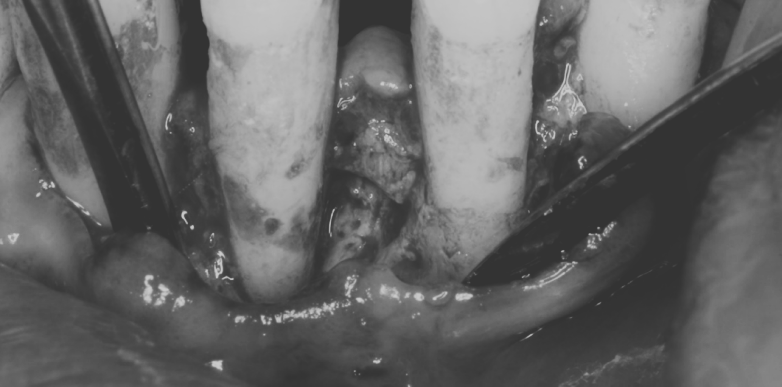

マイクロスコープ精密根管治療と再生療法の併用症例

治療名 【歯周・歯内複合病変】組織再生療法+精密根管治療 治療期間 約1年 執刀医 Dr. 大杉 治療費 420,000円(税込)

■内訳:

再生療法 250,000円

根管治療 130,000円

支台築造 40,000円治療解説 歯の内部と歯周組織の両方に感染が及んでおり、抜歯判断になりやすいケースに対して保存を前提に治療を行いました。

まず精密根管治療で感染源を除去・封鎖し、その後に歯周組織再生療法を実施。

内外の感染を段階的にコントロールすることで、抜歯回避と安定化を目指しました。リスク・副作用 神経(歯髄)を除去するため、歯への栄養供給が断たれ、健全歯に比べて強度が低下します。

硬いものを噛んだ際などに歯根破折のリスクが伴う。 -